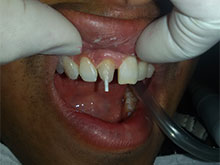

Anterior Implants